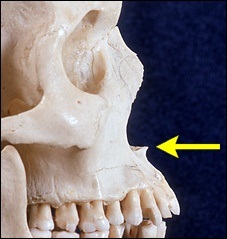

A téma ez a fejezet - acanthion. Acanthion - ez terjed ki előre a csontképződést, található az alapja az orr. A jobb felső fotó rajta a sárga nyíl.

Mielőtt nagyobb acanthion. Ez az, amit úgy néz ki, a művelet során. Az ábrán a jobb ez sárga színű. Acanthion columella található, közvetlenül alatta, ahol a felső ajak határos az alapja az orrát.

A jobb felső sarokban a kép jól látható acanthion (sárga színnel jelöltek). Az alsó képen az azonos, de a távoli nazális gerinc.

A hossza a kék nyíl egyenlő egy hüvelyk.